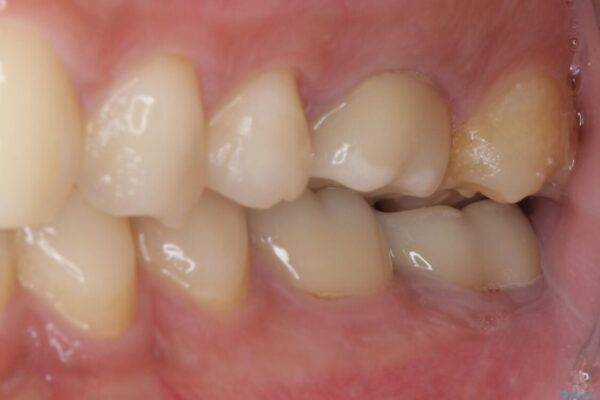

• 海外赴任前に治したい 割れてしまった奥歯のオールセラミッククラウン 治療前画像